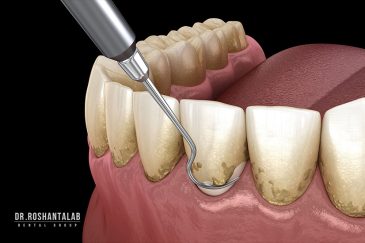

🔸 کاشت ایمپلنت دندان بدون درد

🔸کاشت ایمپلنت فلپ لس یا بدون جراحی و بدون بخیه زیر سه دقیقه

از عصب کشی و درمان ریشه دندان گرفته تا جراحی لثه و کشیدن دندان، تمامی مراحل توسط متخصص ترمیم دندان مدیریت میشود. ارائه باکیفیتترین خدمات ترمیم دندان برای سلامتی شماست.کاشت ایمپلنت فوری دندان